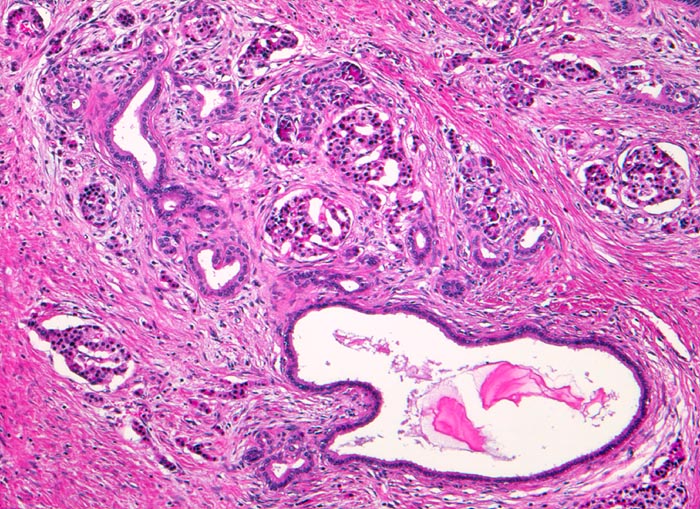

Chronisch-sklerosierende Pankreatitis

Die Azini dieses Lobulus sind weitgehend verschwunden. Neben einigen wenigen atrophen Azini sind zahlreiche Inseln des endokrinen Pankreas zurückgeblieben. Stark dilatierter intralobulärer Gang mit retiniertem Sekret. Daneben proliferierte kleinere Gänge. Minimales Entzündungsinfiltrat.

Alkoholiker mit rezidivierten akuten Pankreatitisschüben. Chronische Diarrhoe.